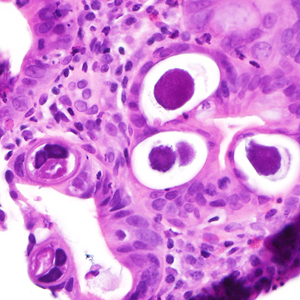

A 25-year-old male was hospitalized for Crohn’s exacerbation, duodenal outlet obstruction, and regional enteritis. He indicated that he has not had recent travel abroad. The patient underwent a gastroenterostomy and duodenal biopsy specimens revealed acute and chronic inflammation with crypt abscesses, focal ulceration, and reactive epithelial changes. Granulomata, epithelial dysplasia, and fibrosis were lacking. The attending pathologist also noted suspect parasitic organisms and the slides were sent to the state health department, which in turn forwarded them to the CDC-DPDx for diagnostic assistance. Figures A–F show what was observed on the slides received for testing. Figure A was taken at 100x magnification; Figures B–D at 400x magnification; and Figures E and F at 1000x magnification with oil. What is your diagnosis? Based on what criteria?

Figure B